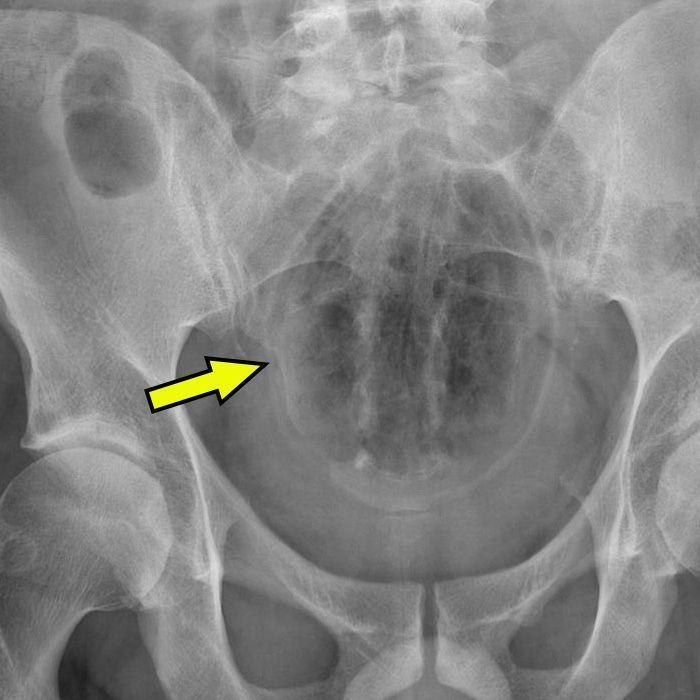

有多超出想象呢?前方即将出现一波令人迷惑又隐隐作痛的X光片。

▷一个玻璃杯

根据《外科年鉴》报道,一位来自密西西比的72岁老农民在附近的垃圾场拉屎。

突然间他的木腿(指木制假肢)折断,导致他“重重地”摔在了玻璃瓶上。

就…挺突然的。